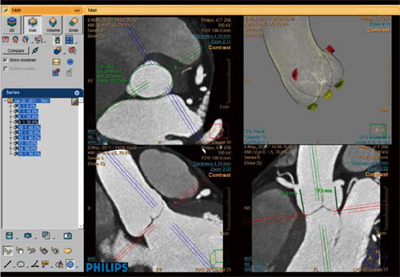

■“ TAVI-Planning”on IntelliSpace Portal ver. 5.0

大動脈弁植え込み術(transcatheteraortic valve implantation:TAVI)は,30~ 40%にのぼる重症の未治療大動脈弁狭窄症4)に対する画期的治療法として注目を集め,2012年にわが国でも治験を終え,2013年に保険承認される可能性が高い。CTは三次元的な客観的データが取得容易なことから,欧米のガイドライン5),6)にもTAVI 術前のCTにおける画像計測の必要性が明記してある。 “TAVI-Planning”(図4)は,専用の解析アプリケーションではなく,ワークステーションIntelli Space Portal(ISP)に標準で搭載されているCardiac Viewerの活用方法である。TAVI 術前情報として必須になる大動脈弁の弁口面積,石灰化の程度,デバイス選択のための大動脈弁輪の直径,面積や周囲長,弁先端部~冠動脈起始部の距離,アプローチする血管の径,動脈硬化の広がりや湾曲の程度,さらに血管撮影装置のアンギュレーションなどの一連の解析が可能である。

Cardiac Viewerはその名の通り,循環器画像に特化した作り込みがされており,複数心位相の同時比較表示やシネモード,アキシャル像に同期した撮影時心電図波形の参照や,Area Length法による心機能解析が行える。なかでも定評のある機能に,心軸(短軸,垂直・水平長軸)の自動MPR作成機能がある。コロナルやサジタルがワンクリックで切り替わるビューワは珍しくないが,心軸への自動切り替えは大変ユニークな機能であると言える。

図4 TAVI-Planning の解析画面